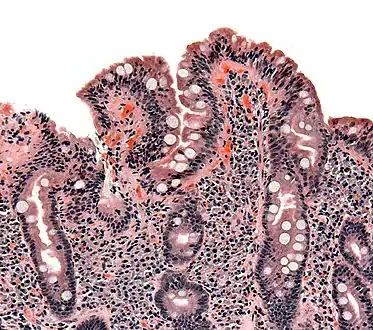

| Whipple's disease: Alcian blue with apparently eosin counterstain enlarged villus with many macrophages | |